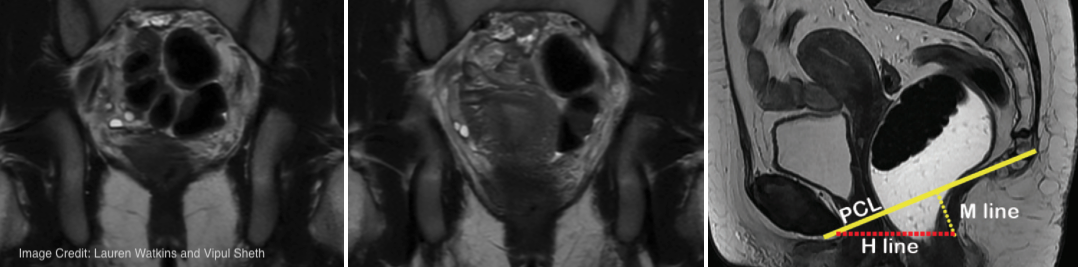

PI: Feliks Kogan | Radiology

Physical activity is generally thought to improve postpartum health, but returning too soon or too intensely may increase the risk of pelvic floor disorders. Current guidelines recommend gradual progression in activity intensity and impact but lack specificity and may be too conservative for athletes. Proposed return-to-run protocols exist, but there’s little objective evidence on pelvic floor healing timelines to support them. This project will use MRI to measure pelvic floor recovery in runners from 6 weeks to 6 months postpartum, relating physiologic changes to symptoms and physical activity data from wearables and motion analysis. Comparisons with women who haven’t given birth will help establish recovery benchmarks. This preliminary data could inform evidence-based return-to-activity protocols for postpartum women and athletes.